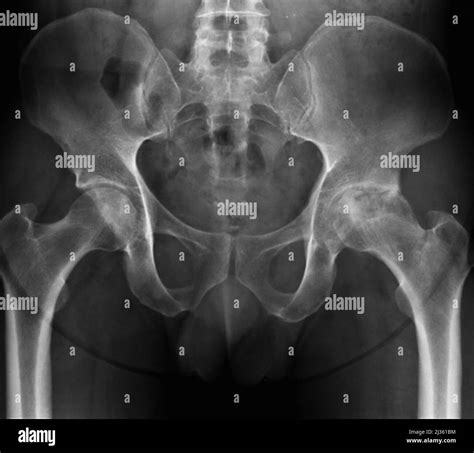

Diagnosing osteoarthritis typically involves a few key steps. Your doctor will start by asking about your medical history and your symptoms . They’ll want to know when the pain started, what makes it better or worse, and if you have any other health conditions. Then comes the physical examination . The doctor will look at your affected joint(s) for swelling, redness, and tenderness. They’ll also gently move your joint to check its range of motion and listen for any crepitus. To get a clearer picture of what’s going on inside, imaging tests are often used. X-rays are the most common. They can show you the extent of cartilage loss, bone spurs, and narrowing of the joint space. Sometimes, other imaging like an MRI might be ordered, especially if there’s suspicion of other soft tissue damage or if X-rays aren’t clear. In rare cases, if the diagnosis is uncertain or to rule out other conditions like infection or gout, your doctor might order a joint fluid analysis . This involves drawing a small sample of fluid from the affected joint using a needle and testing it in a lab. But for most people, a combination of your history, a physical exam, and X-rays is enough to diagnose osteoarthritis.